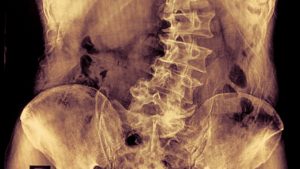

脊柱侧弯是脊柱出现大于10度的C型或S型的非正常弯曲。脊柱侧弯的类型包括特发性脊柱侧弯、先天性脊柱侧弯、综合征型脊柱侧弯等。其中,儿童青少年特发性脊柱侧弯是最为常见的类型。

如果发生脊柱弯曲异常,可能存在如穿衣服两个领子不平,或者一个肩高一个肩低,或者后背有隆起,或者脱衣服以后皮肤一侧皱褶,甚至骨盆髋部一高一低。